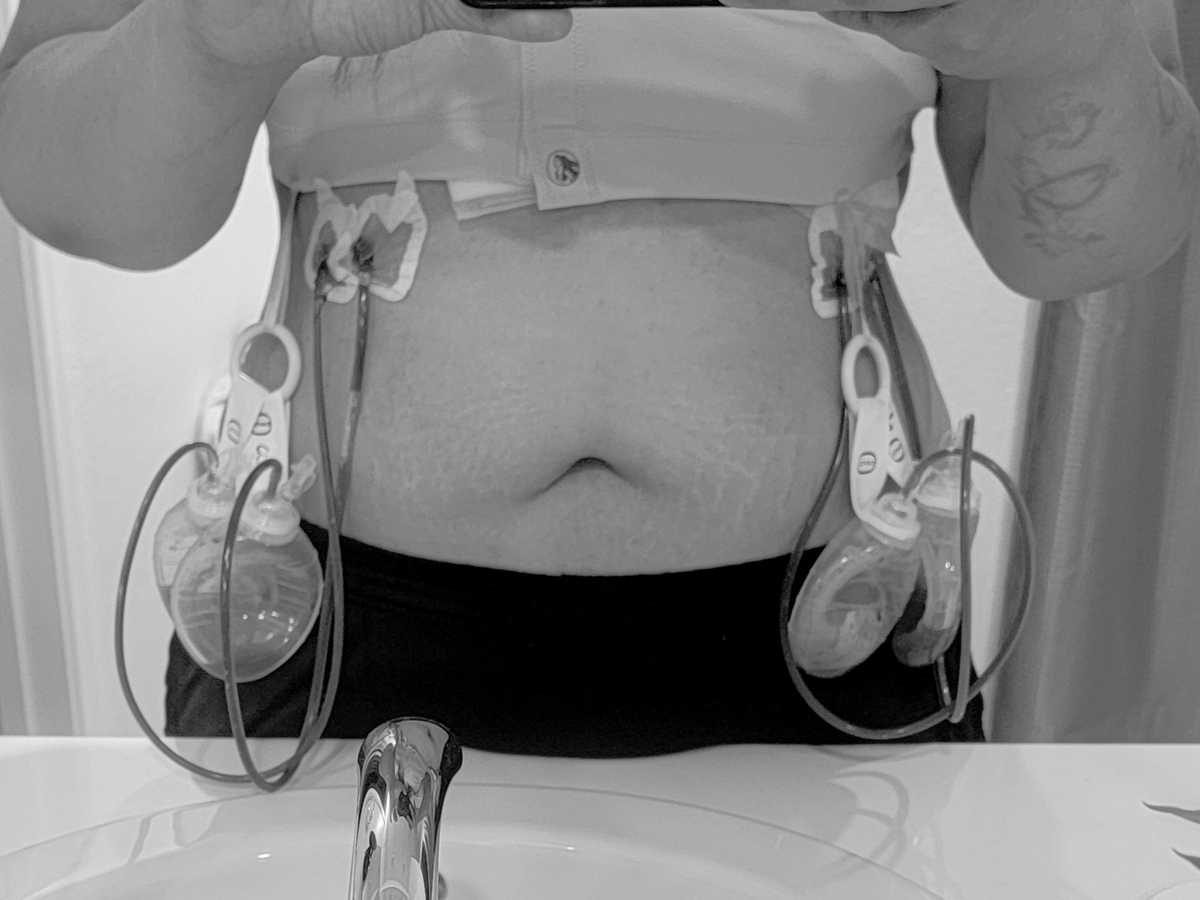

In April, my wife found a lump in my right breast. I quickly dismissed it. I thought it had to be nothing, I was only 38. She made me make an appointment anyways. After 2 mammograms, an ultrasound and a biopsy, I got a call. By the end of May they confirmed it was breast cancer. When I got the news, all I could think, was damn...thats a bummer, It blindsided me because i really made myself believe it was nothing. And then I realized I'd have to tell my wife and my mom, and everyone. Cancer wasn't going to just change my life, but it would the lives of everyone who loved me. After more tests and doctors visits and making really hard surgical decisions, I finally had a surgery date, August 19th. Thats the day cancer took both of my breasts. Double mastectomy, lost 4 lymph nodes and preparation of reconstruction. But I'm here, the first part is done. Its very painful, as one could imagine. Not just physically painful but also mentally painful. I didn't ask for cancer, but it came anyways. I didn't want to have a full mastectomy but it was necessary. I didn't want my body dissected but it saved my life. So its a little hard to look in the mirror right now, but I'll get there. This journey will be a little long and painful. I wont be at work for some time. So my family wanted to start this gofundme page to help me while I focus on my health. My family and I ask if you could please share this page for donations and share my story. And please encourage yourselves and your loved ones to see the doctor and stay on top of your health because life is too beautiful to miss.